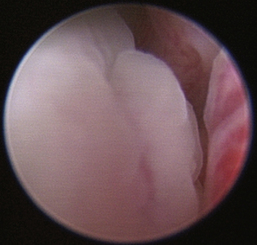

There are many nonspecific changes seen with rhinoscopic evaluation that vary from mild to severe (Figures 19-34 through 19-41). Mucosal hyperplasia, hyperemia, and accumulations of mucoid to mucopurulent secretions are typical findings. Turbinate mucosa can have a classic clubbed and hyperplastic appearance. Progression can result in generalized or polypoid mucosal proliferation or hyperplasia. In severe, chronic cases, infected and necrotic turbinate can be seen. The combination of mucosal hyperplasia and abundant accumulation of mucus compromises the air passageways and can limit the movement of the scope, especially in cats and small dogs. Inflamed tissue bleeds easily and can further decrease visibility. Site selection for biopsy is often nonspecific because most of the nasal mucosa is involved. Bacterial cultures collected at the time of examination may reveal a current secondary bacterial infection, unlikely the primary cause but nonetheless creating pathologic symptoms. Mycoplasma may be of concern in cats with recurring rhinitis.35 Biopsy and appropriate culture submission are critical for developing a specific medical plan to manage the patients’ current symptoms.

image

Figure 19-34 Canine lymphoplasmacytic rhinitis with hyperplasia with turbinate clubbing.

Figure 19-35 Canine lymphoplasmacytic rhinitis with mucosal hyperplasia and turbinate clubbing.

Figure 19-36 Canine severe and chronic lymphoplasmacytic rhinitis with polypoid mucosal hyperplasia.

Figure 19-37 Canine severe and chronic lymphoplasmacytic rhinitis with inflammatory bridging of turbinates.

Figure 19-38 Canine severe chronic lymphoplasmacytic rhinitis with polypoid masses.

Figure 19-39 Feline lymphoplasmacytic rhinitis with polypoid hyperplasia.

Figure 19-40 Feline lymphoplasmacytic rhinitis with caseated obstructive mucus.

Figure 19-41 Feline lymphoplasmacytic rhinitis; caseated obstructive mucus recovered during rhinoscopy with curettage and traumatic flushing.